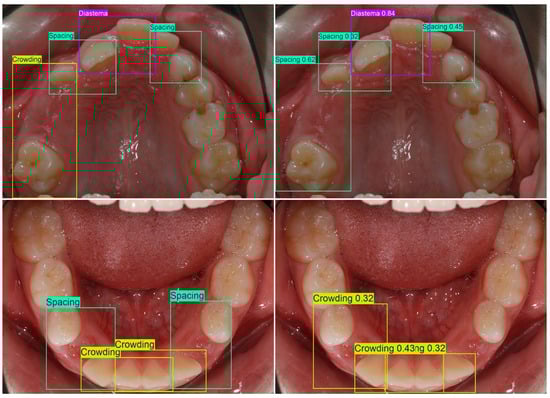

Multi-Class Malocclusion Detection on Standardized Intraoral Photographs Using YOLOv11

Background/Objectives: Accurate identification of dental malocclusions from routine clinical photographs can be time-consuming and subject to interobserver variability. A YOLOv11-based deep learning approach is presented and evaluated for automatic malocclusion detection on routine intraoral photographs, testing the hypothesis that training on a structured annotation protocol enables reliable detection of multiple clinically relevant malocclusions. Methods: An anonymized dataset of 5854 intraoral photographs (frontal occlusion; right/left buccal; maxillary/mandibular occlusal) was labeled according to standardized instructions derived from the Index of Orthodontic Treatment Need (IOTN) A total of 17 clinically relevant classes were annotated with bounding boxes. Due to an insufficient number of examples, two malocclusions (transposition and non-occlusion) were excluded from our quantitative analysis. A YOLOv11 model was trained with augmented data and evaluated on a held-out test set using mean average precision at IoU 0.5 (mAP50), macro precision (macro-P), and macro recall (macro-R). Results: Across 15 analyzed classes, the model achieved 87.8% mAP50, 76.9% macro-P, and 86.1% macro-R. The highest per-class AP50 was observed for Deep bite (98.8%), Diastema (97.9%), Angle Class II canine (97.5%), Anterior open bite (92.8%), Midline shift (91.8%), Angle Class II molar (91.1%), Spacing (91%), and Crowding (90.1%). Moderate performance included Anterior crossbite (88.3%), Angle Class III molar (87.4%), Head bite (82.7%), and Posterior open bite (80.2%). Lower values were seen for Angle Class III canine (76%), Posterior crossbite (75.6%), and Big overjet (75.3%). Precision–recall trends indicate earlier precision drop-off for posterior/transverse classes and comparatively more missed detections in Posterior crossbite, whereas Big overjet exhibited more false positives at the chosen threshold. Conclusion: A YOLOv11-based deep learning system can accurately detect several clinically salient malocclusions on routine intraoral photographs, supporting efficient screening and standardized documentation. Performance gaps align with limited examples and visualization constraints in posterior regions. Larger, multi-center datasets, protocol standardization, quantitative metrics, and multimodal inputs may further improve robustness. Full article